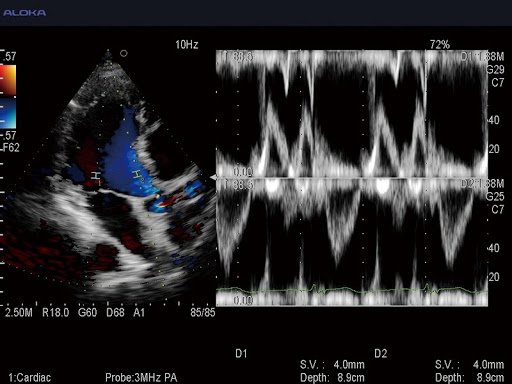

- Flow - цветной допплер

- PW - импульсно-волновой допплер

- Dual Doppler - двойной допплер (два одновременных контрольных объёма в режимах PW и TDI)

- Дуплексные и триплексные режимы